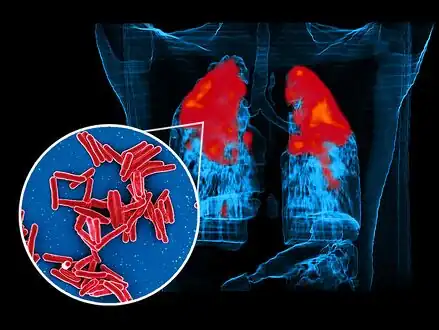

Scanning electron micrograph of Mycobacterium tuberculosis bacteria, which cause TB foreground image and a PET/CT scan showing TB infection (red) in an individuals lungs background image -